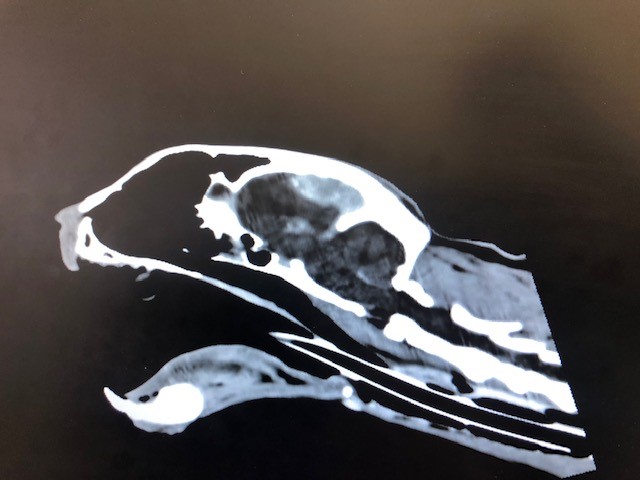

Mein Kater hat leider durch einen Zufallsbefund die Diagnose Hirntumore bekommen. Balou ist 15 Jahre alt und deshalb würde ich mich gegen eine OP entscheiden. Nun habe ich bereits sehr oft gelesen das man alternativ mit Vtalpilzen behandeln könnte.. Mit dem Agaricus Blazei und dem Maitake.